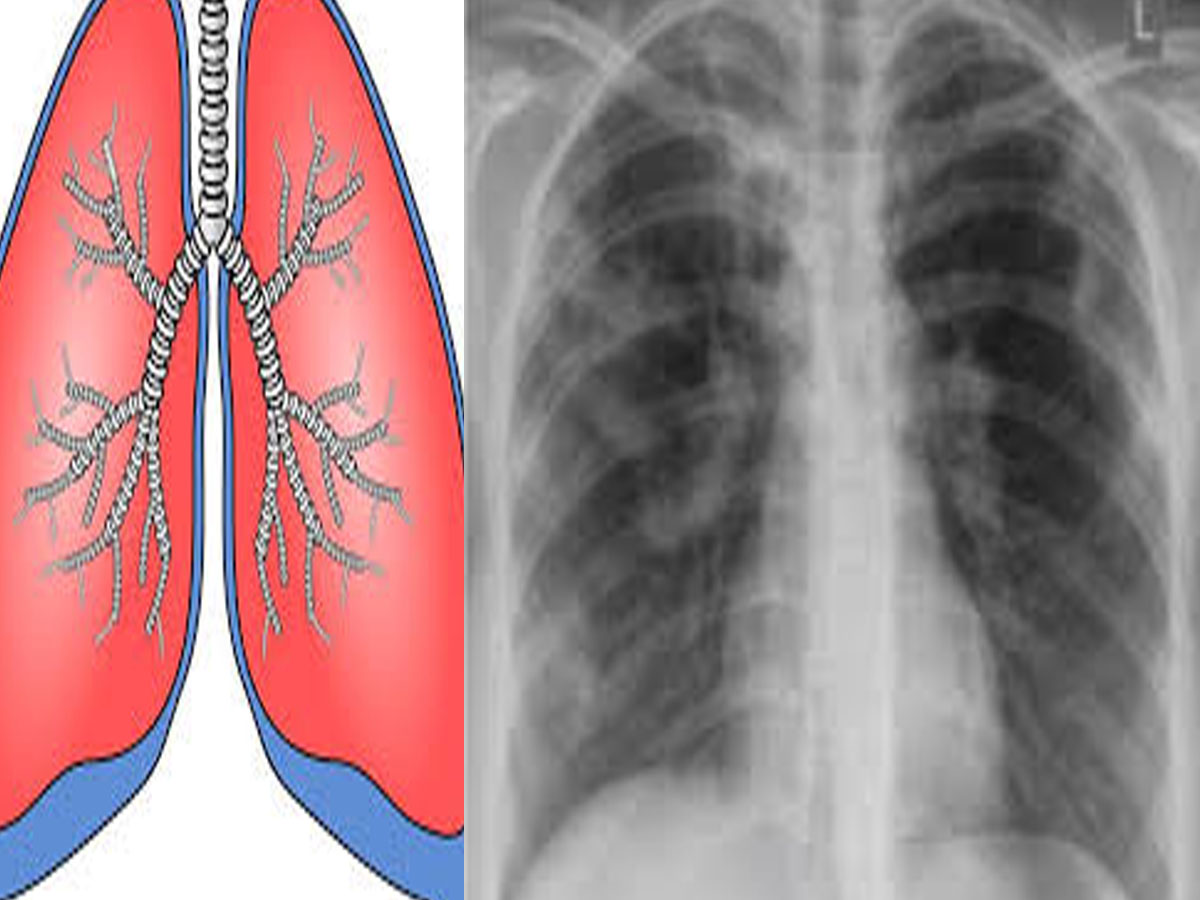

Dungarpur News: डूंगरपुर जिले में टीबी बीमारी को लेकर सुखद खबर है. डूंगरपुर जिले में साल दर साल टीबी के मरीजो की संख्या में कमी हो रही है. विभाग की ओर से की गई जांच में वर्ष 2021 में 25 फीसदी, वर्ष 2022 में 21 फीसदी, वर्ष 2023 में 17 फीसदी और वर्ष 2024 मई तक 6 फीसदी मरीज टीबी से ग्रसित पाए गए है.

एचआइवी (एड्स) के बाद दूसरी सबसे ज्यादा खराब बीमारी टीबी को माना जाता है क्योंकि अगर इसका समय से सही इलाज न हुआ तो यह जानलेवा भी हो जाती है. जानलेवा इस बीमारी को भारत से खत्म करने के लिए सरकार द्वारा चलाये जा रहे प्रयासों के सार्थक परिणाम सामने आने लगे हैं. डूंगरपुर क्षय रोग निवारण केंद्र की प्रभारी डॉ करिश्मा पंचाल ने बताया की वित्तीय वर्ष 2019-20 में 4208 मरीज थे. वित्तीय वर्ष 2020-21 में यह संख्या घटकर 2869 पर आ गई.

उन्होंने कहा कि वहीं इसके बाद प्रति वर्ष इन आंकड़ों में कमी आती जा रही है. वर्ष 2021-22 में विभाग की ओर से 7 हजार 377 लोगों की टीबी की जांच की गई जिसमें 1869 मरीज टीबी के पाए गए. इसी तरह वर्ष 2022 में 14 हजार 869 जांच की गई जिसमें 21 फीसदी मरीज टीबी के आये तो वही वर्ष 2023 में 20 हजार 567 जांच की गई जिसमे से 17 फीसदी मरीज टीबी के निकले. इधर डॉ करिश्मा ने बताया की वर्ष 2024 में अभी तक 24 हजार 798 जांच की गई जिसमें 6 फीसदी टीबी के मरीज सामने आये है. उन्होंने बताया कि सरकार द्वारा चलाए जा कार्यक्रमों का ही परिणाम है की इस रोग के मरीजों की संख्या लगातार घट रही है.